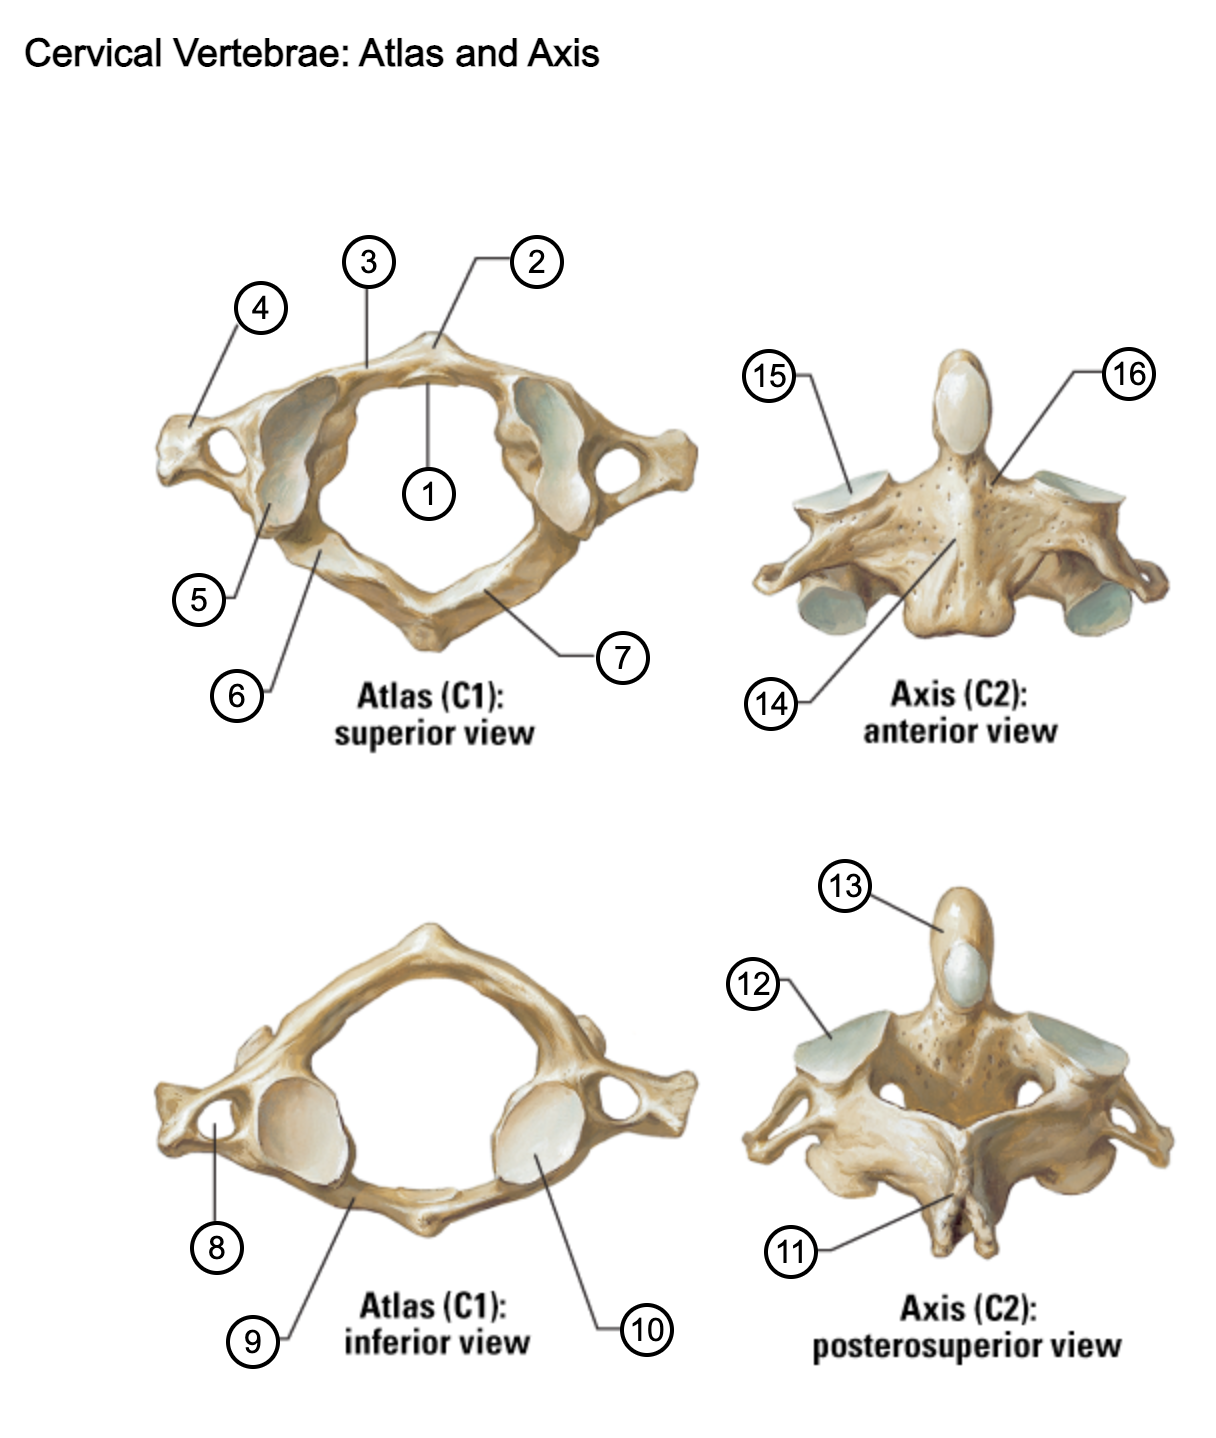

1

facet for dens

2

anterior tubercle

3

anterior arch

4

transverse process

5

superior articular surface of atlas

6

groove for vertebral artery

7

posterior arch

8

transverse foramen

9

anterior arch

10

inferior articular surface of atlas

11

spinous process

12

superior articular facet

13

dens of axis

14

body of axis

15

superior articular facet for atlas

16

pedicle of vertebral arch